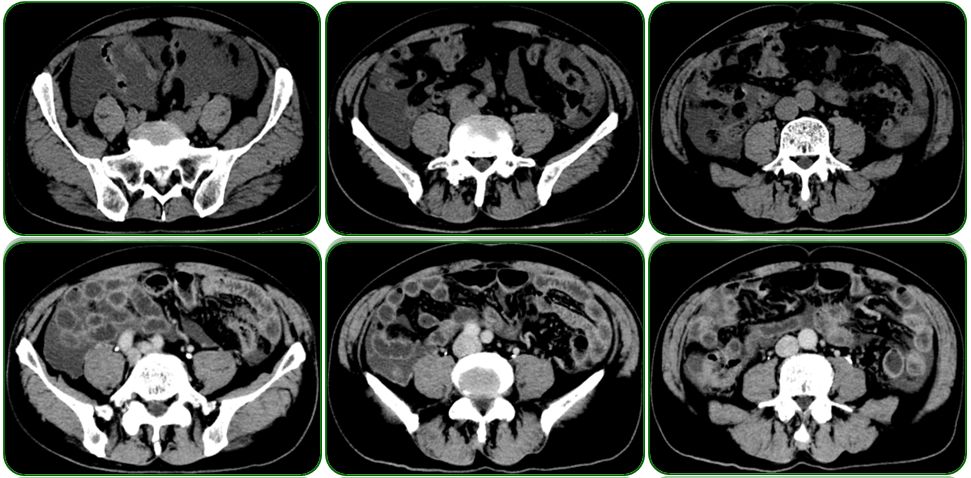

外院胃镜检查见吻合口粘膜充血水肿,残胃未见溃疡及肿物,如图1;

图1 胃镜检查

就在这个时候我们突然发现外院胃镜有点蹊跷,如图1吻合口粘膜有点问题,粘膜粗糙隆起,由于是在外院做的胃镜我们不能全面评估吻合口情况,因此建议患者重新复查胃镜,如图8。复查胃镜发现吻合口前壁黏膜隆起,表面稍粗糙,于是做了病理活检。病理结果提示低分化腺癌,部分为印戒细胞癌。到此为止,该患者诊断才算明确:残胃癌、腹盆腔转移。既然诊断明确了,治疗就有据可依。